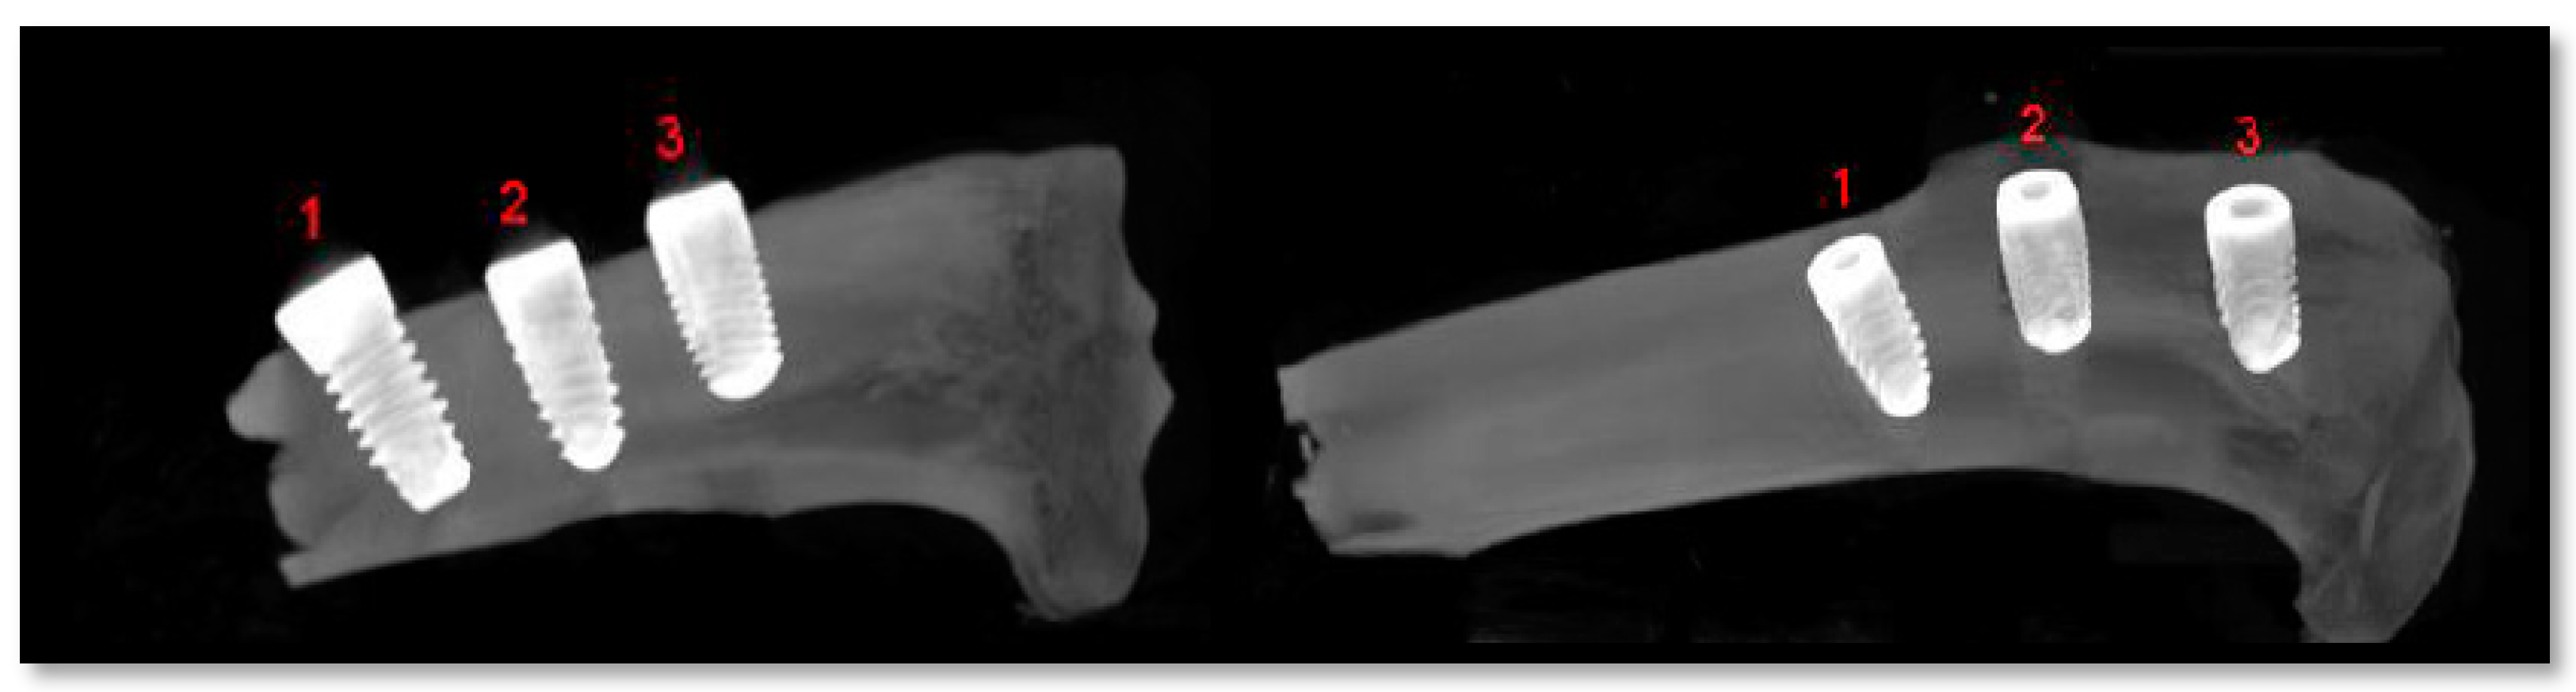

2.5. Radiological Analysis

3.3. Experimental Animal Study